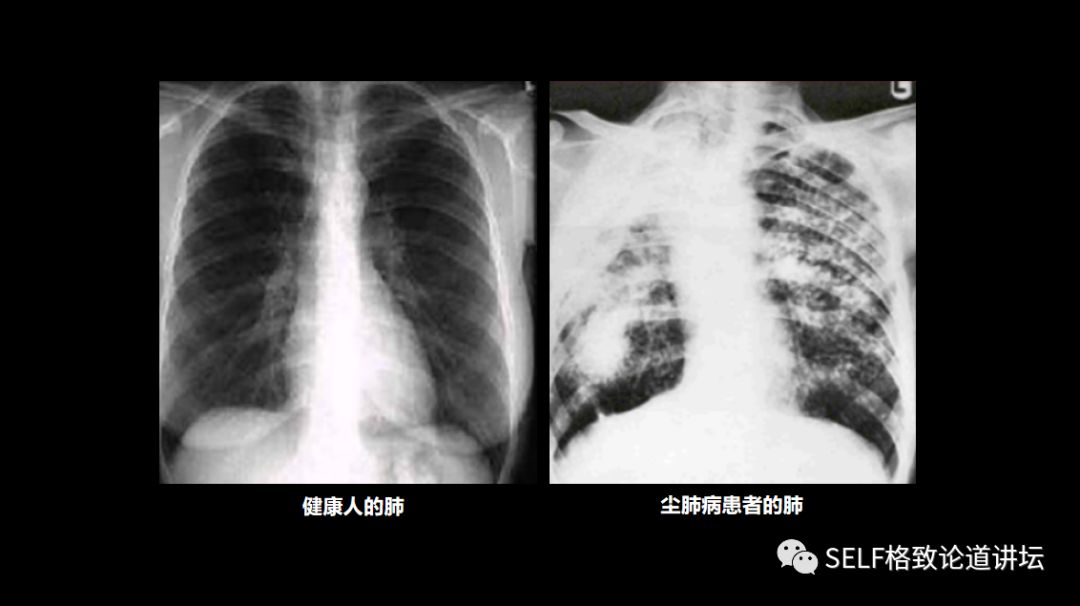

这是正常的肺照片和有尘肺病的照片,与标本里面所提到的一些,像石棉肺、煤工尘肺和矽肺都是比较常见的尘肺病的分类,这里面不同的颜色都是病灶所在。

通过和正常的肺脏相比,可以看到它的形态、大小、颜色都有变化,实际上它的功能也受到很大的影响。

在X光片下,可以看得更加明显,左边是正常的肺脏照片,肺组织里面干干净净的,什么都没有。如果是一个尘肺病患者的照片,在X光片上就可以看到不同的小阴影、大阴影,实际上这些都是粉尘在肺组织里逐渐凝聚、增多而造成的。

那么这部分肺组织慢慢就会失去功能,人们能提供有效呼吸的肺组织的数量就会特别少,呼吸功能就会慢慢地下降,导致病人的抵抗力逐渐下降,呼吸功能严重受损。